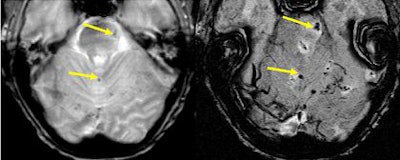

SWI's sensitivity to iron may open a new door into detecting lesions and the study of lesion specificity in MS.

| The far left and far right images are T2-weighted and both show numerous lesions. Some are seen on SWI and some are not in the SWI filtered phase images. However, some are seen better with SWI as dark regions (high iron content), and these may eventually be shown as markers for the specificity of the disease. Image courtesy of E. Mark Haacke, Ph.D., Wayne State University, Detroit. |